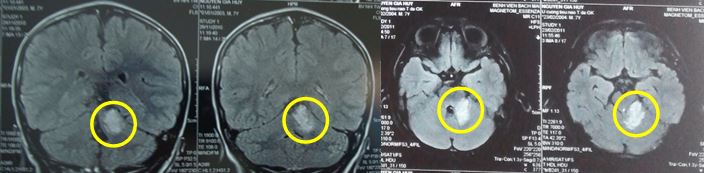

Kết quả chụp cộng hưởng từ sọ não cho thấy:

Hình ảnh cộng hưởng sọ não từ trước điều trị: Kích thước khối u: 3,2 x 2,8cm

Hình ảnh cộng hưởng từ sọ não sau xạ phẫu 3 năm: Khối u đáp ứng tốt, chỉ còn hình ảnh tăng tín hiệu nhẹ trên T2, không ngấm thuốc đối quang từ, kích thước 0,8 x1cm